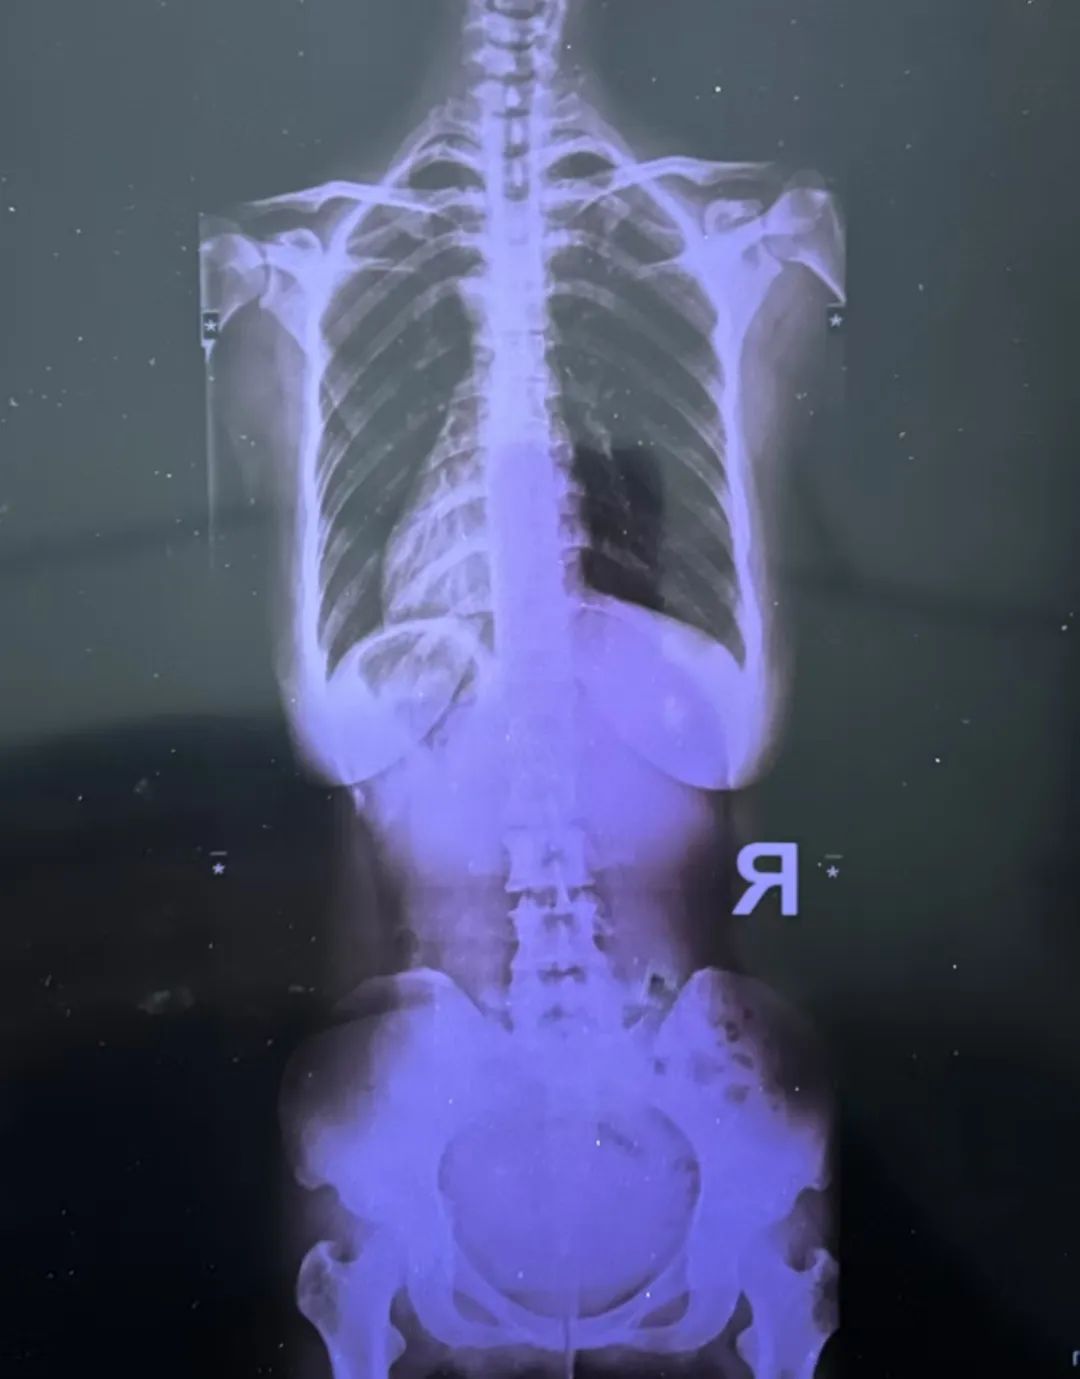

最近又疼起來(lái)嚴(yán)重影響正常生活,她前往醫(yī)院就診,結(jié)果查出了脊柱側(cè)彎11°,骨盆旋移,骶髂關(guān)節(jié)半脫位,由于這些導(dǎo)致頸肩,后背,腰部肌群代償出現(xiàn)問(wèn)題,從而出現(xiàn)腰痛,后背痛,肩膀痛!